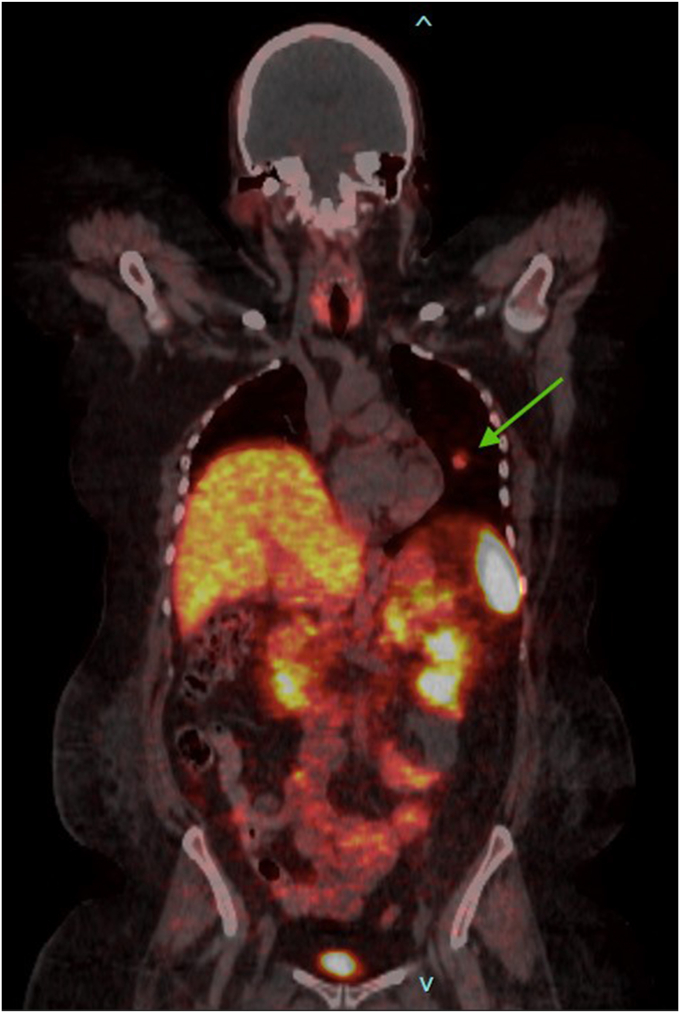

A 32-year-old woman developed diabetes, hypertension, and weight gain of 50 pounds over 3 months. Laboratory evaluation was significant for elevated cortisol and adrenocorticotropic hormone levels and levels were nonsuppressible on low and high-dose dexamethasone suppression tests. Chest computed tomography revealed a pulmonary nodule and biopsy showed a typical carcinoid tumor. She was treated with steroidogenesis inhibitors with a plan for surgical excision but developed worsening complications of hypercortisolemia. She eventually underwent cryoablation of the tumor, but unfortunately passed away just 6 months after her initial presentation.